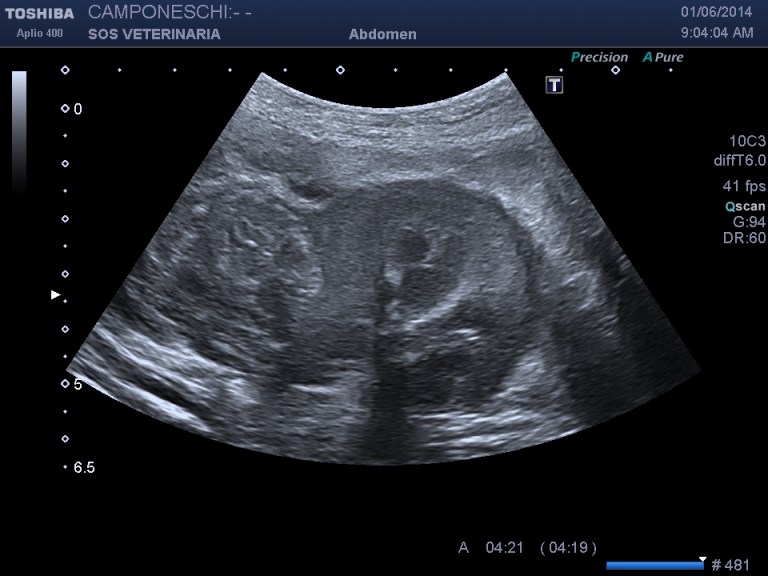

Beagle maschio 13 aa di nome Teo ,insorgenza iperacuta dopo trauma di lieve entita’ (caduta da un muretto alto meno di 1 metro) di sindrome algica addominale acuta ,l’esame ecografico mostra massa irregolare , disomogenea perirenale sx profilo d’organo irregolare e alterato con severa perdita di tessuto corticale ,quadro compatibile con grave infarcimento necrotico- emorragico , eseguito esame ceus ,ha confermato l’avascolarita’ della lesione ,in diagnosi differenziale e’ stato considerato emangiosarcoma renale con rottura secondaria al trauma .

milza lesione focale eterogenea

La minima entita’ del trauma ci ha fatto sospettare un emangiosarcoma allo stesso modo di quello splenico in pronto soccorso molto comune alla presentazione . dopo stabilizzazzione di 48 ore e’ stata eseguita nefrectomia .L’esame istopatologico ha escluso un emangiosarcoma e diagnosticato un grave e severo infarcimento necrotico-emorragico con distruzione del 30 % della massa renale ,si ipotizza la rottura di una anomalia presistente forse vascolare per la minima entita’ del trauma che non spiegherebbe se non come eccezione la gravita’ del quadro ..

Un’altra considerazione riguarda la Ceus che in questo caso non ha fornito altre indicazioni se non la conferma di una vasta lesione infartuale emorragica, forse in caso di emangiosarcoma, la presa del contrasto nella corteccia confinante sarebbe stata disomogenea e non netta la demarcazione tra tessuto sano e patologico ,le lesioni epatiche sono state prima dell’intervento campionate in citologia e nonostante fossero ipoenanchment in tutte le fasi sono risultate benigne di natura rigenerativa .